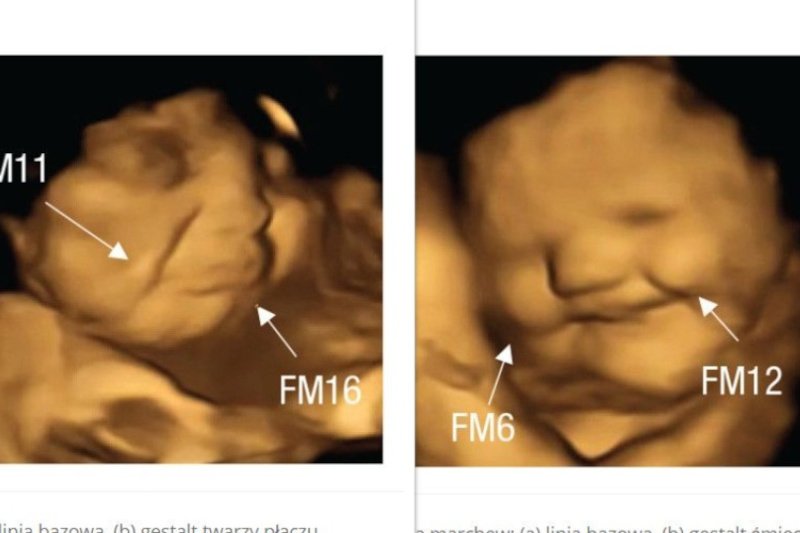

Naukowcy z LaboratoriumBadań nad Płodem i Noworodkiem z Durham University opublikowali badania, w których obserwowali na żywo reakcje płodu na różne pokarmy podawane matkom. 70 ciężarnych w wieku od 18 do 40 lat podzielono na dwie grupy kontrole, z których jedna połykała kapsułkę z wyciągiem z jarmużu, druga z marchwi. Zdjęcia USG płodów badanych kobiet porównano także z 30 skanami archiwalnymi.

Wyniki okazały się bardzo ciekawe. Płody, którym podawany był jarmuż, dwa razy częściej robiły grymasy twarzy przypominające płacz, niż te u matek, które nie połykały jarmużu lub jadły marchew. W odwrotnej sytuacji, gdy matka połykała kapsułkę ze sproszkowaną marchwią, płody były o wiele bardziej zadowolone.

Naukowcy zbadali 180 skanów 99 płodów, skanowanych w 32., 36. tygodniu lub w obu punktach czasowych.